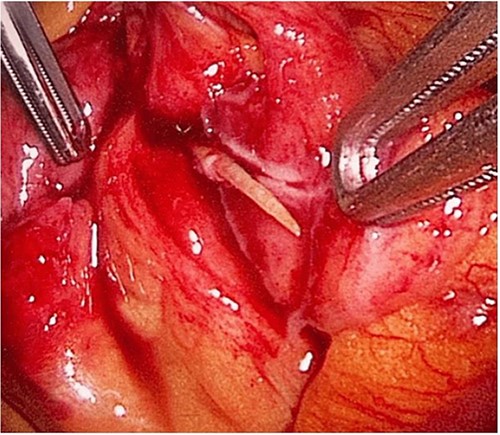

During her hospital stay, the patient showed no improvement regarding abdominal pain, nausea, or abdominal exam. Therefore, she was offered a laparoscopic exploration to verify the diagnosis of a FB to which she agreed. She was taken to the operating room, and the exploration showed an inflammatory process in the LLQ (Fig. 3) with the sigmoid colon attached to the area of the inflammatory reaction. A FB was found in the mesentery of two loops of the ileum 100 cm from the ileocecal junction (Figs 4 and 5). Removal of the FB safely and milking of the small bowel showed no leakage of bowel contents (Fig. 6). And, exploring the rest of the abdomen showed no other pathology and normal ovaries (Figs 7 and 8); the procedure was uneventful. The FB was identified as a toothpick, 3 cm in length (Fig. 9).

The laparoscopic exploration showed a FB in the mesentery of two loops of the ileum 100 cm from the ileocecal junction—after full exposure of the site of the toothpick.